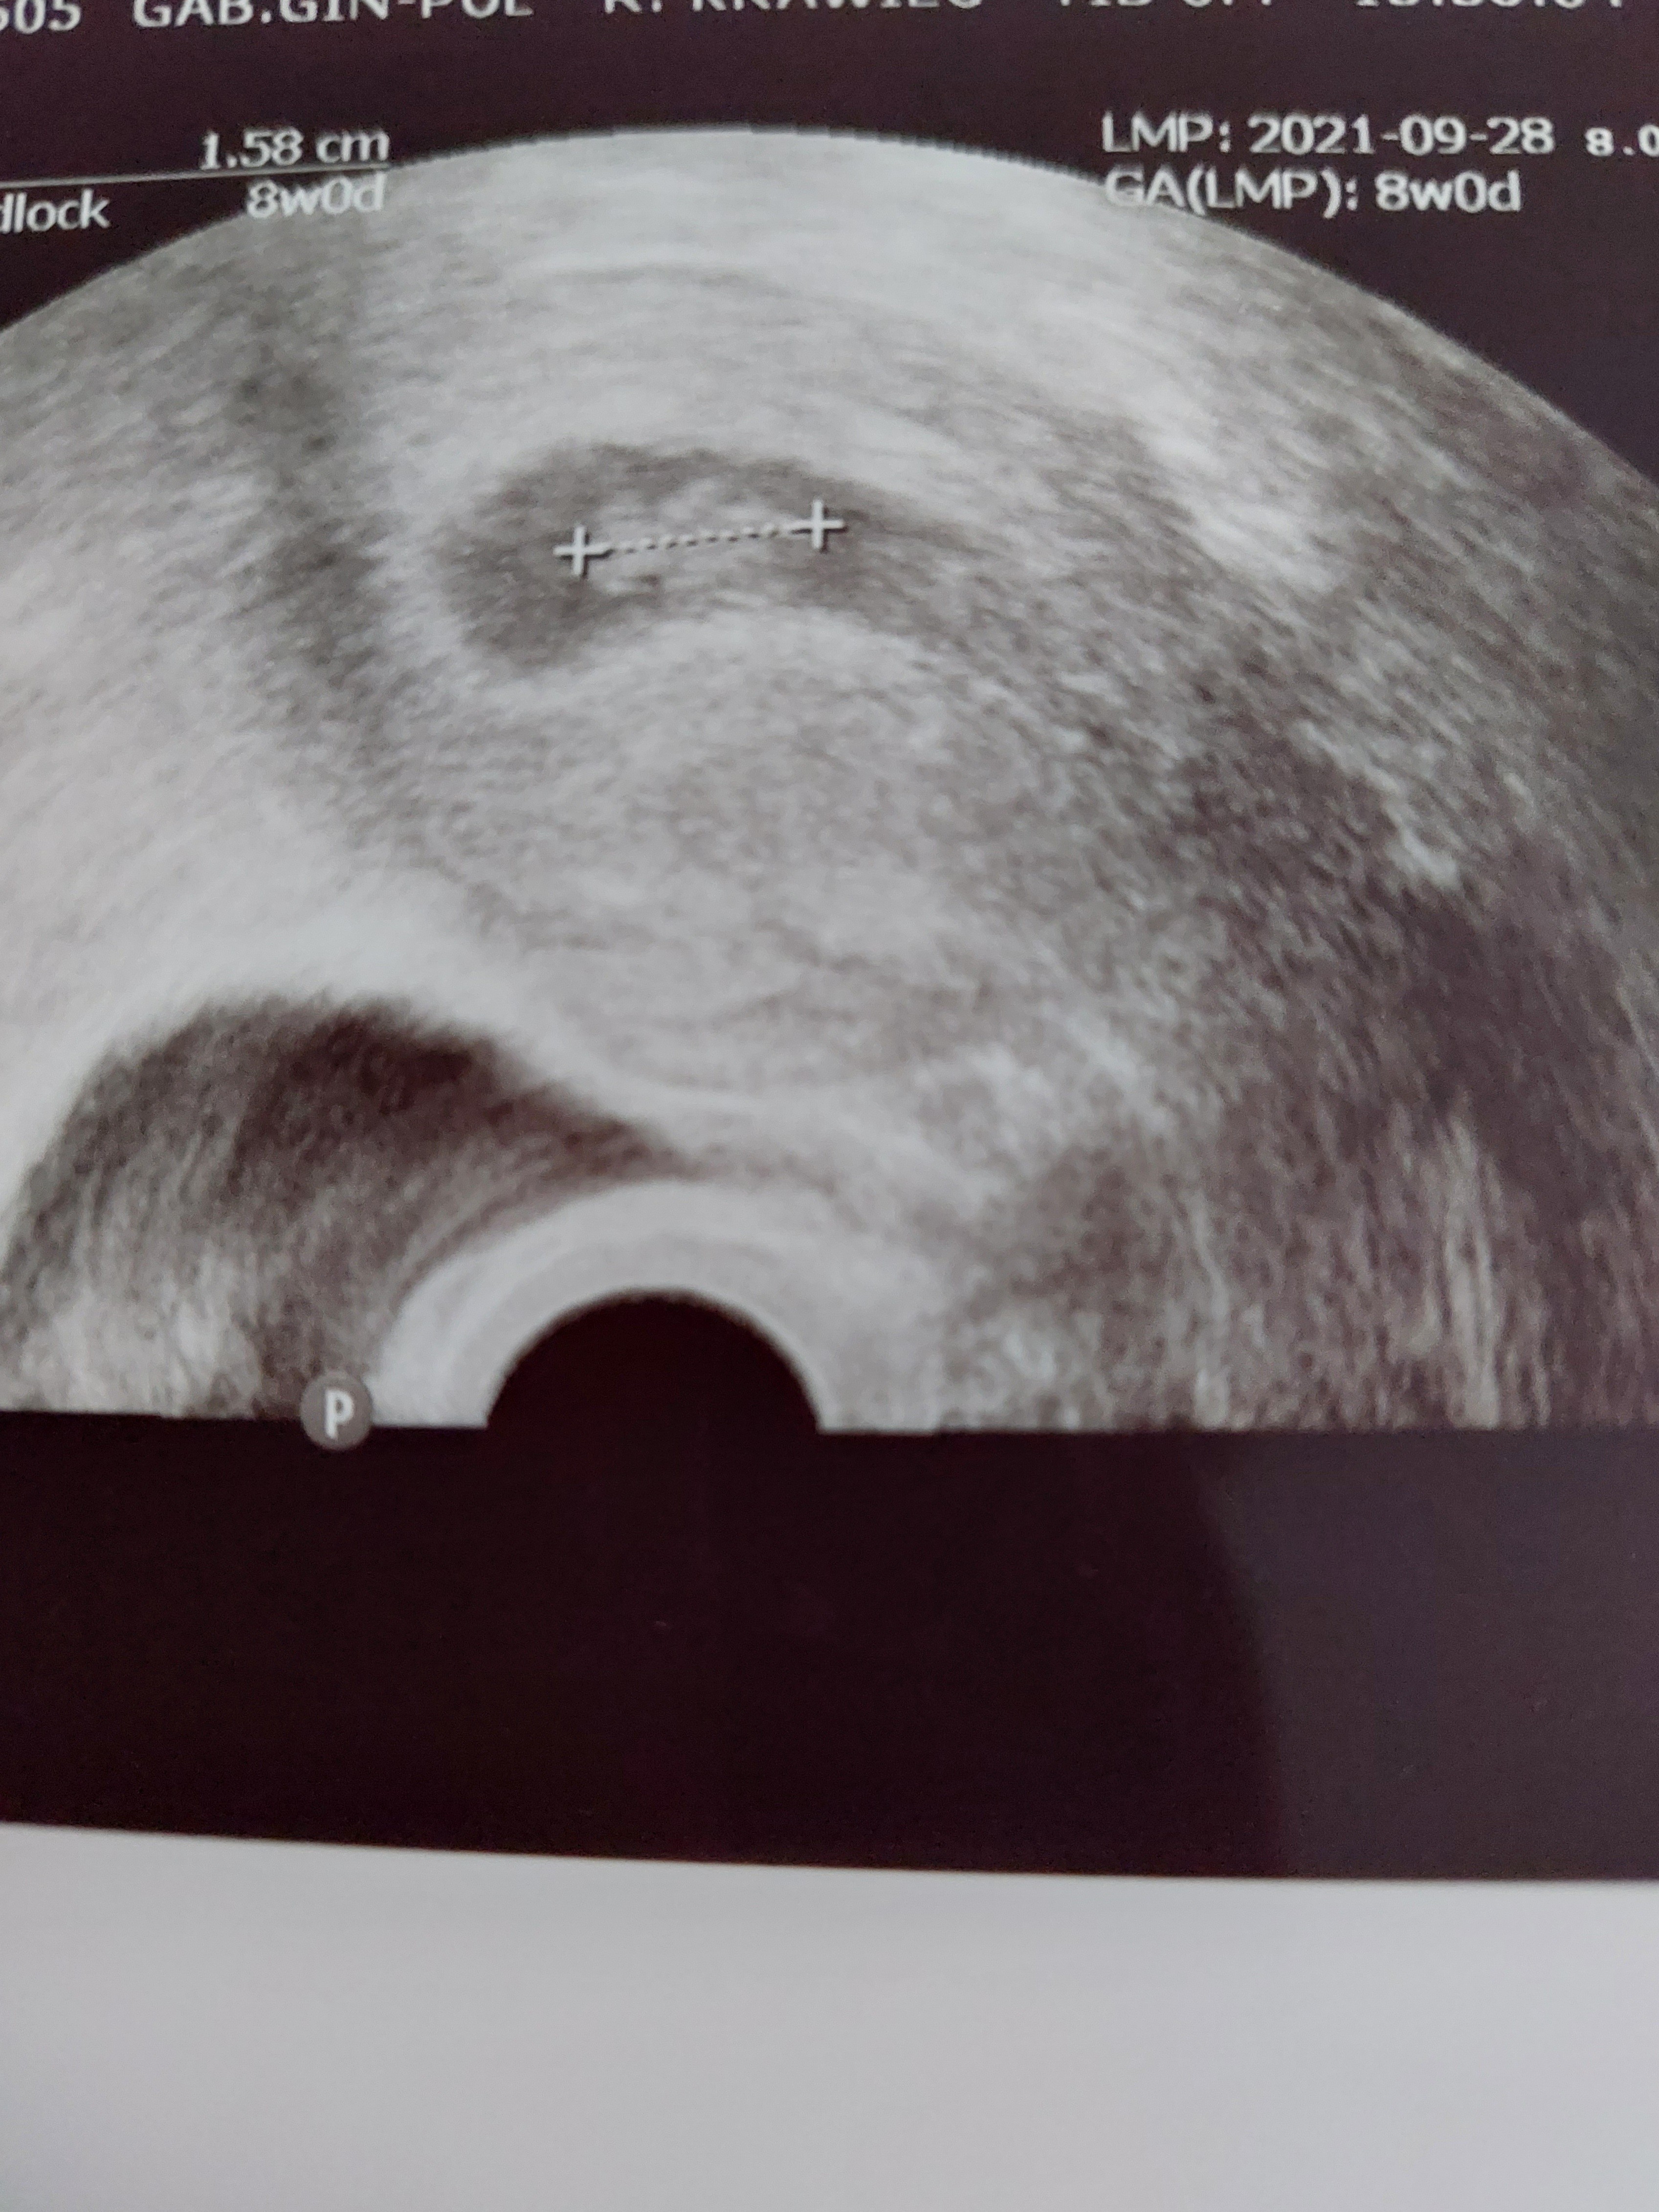

• 20211123_143717.jpg

20211123_143717.jpg

2,3 MB · Wyświetleń: 138